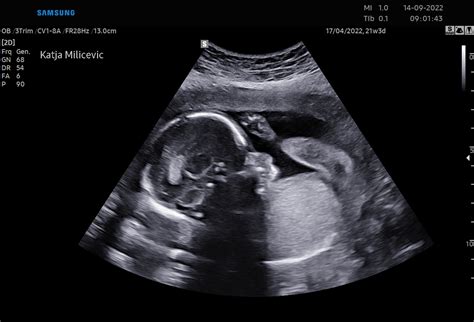

V tem tednu nosečnosti vaš otrok meri približno 28 cm od temena do trtice in tehta okoli 1,5 kilograma. Kljub temu, da se njegova rast nekoliko upočasnjuje, še vedno pridobiva na teži, v povprečju okoli 200 gramov na teden, kar pomeni, da bo do konca nosečnosti pridobil še dodatnih 1 do 1,5 kilograma. Trenutno tehta polovico tistega, kar bo tehtal ob rojstvu, do konca pa ima še nekaj centimetrov.

Medtem ko se otrok še ni premaknil v končni položaj za porod, se bo postopoma pomikal bližje steni maternice, njegova glava pa se bo začela premikati proti izhodu. Idealno je, da je otrok pred začetkom popadkov obrnjen z glavo navzdol proti materničnemu vratu. Babica bo od zdaj naprej redno preverjala otrokov položaj.